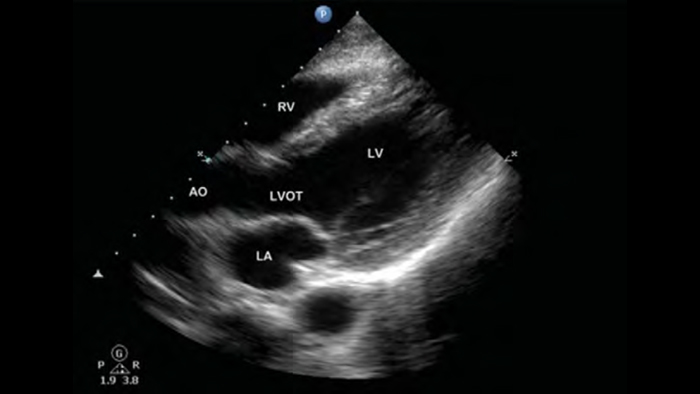

• 2D, color Doppler, M-mode, advanced XRES and multivariate harmonic imaging

• High-resolution imaging for abdominal and cardiac applications: Cardiac, OB/GYN, Lung, Abdomen and FAST imaging preset optimizations